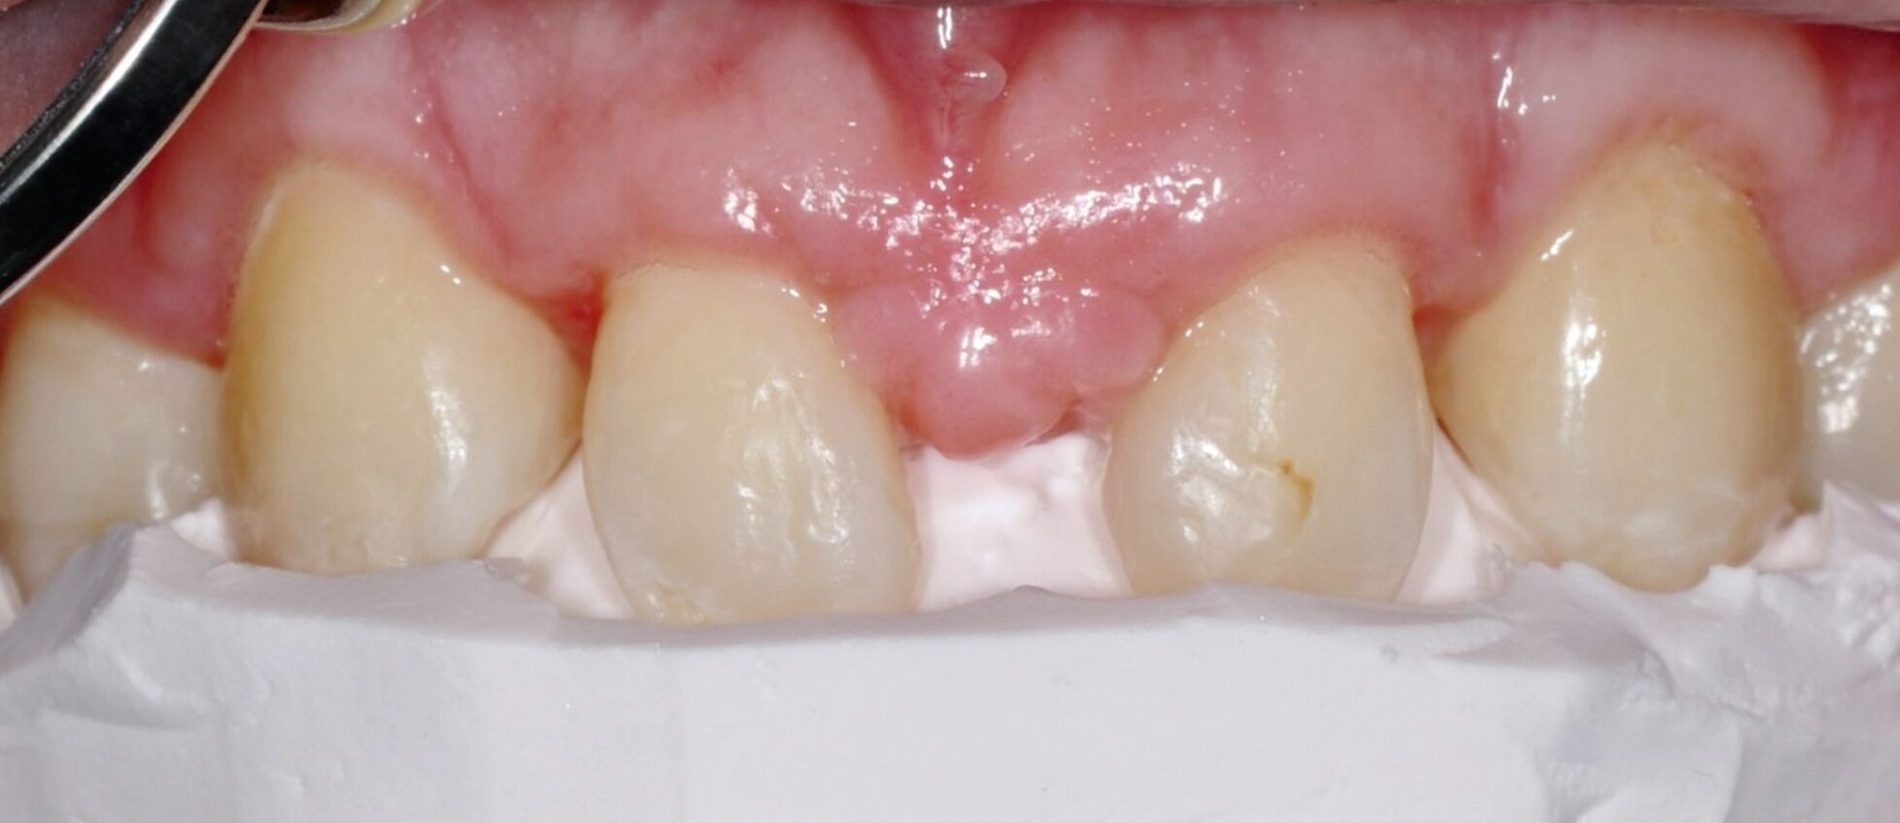

Bei der Erstvorstellung zeigt der Patient ein ausgeprägtes Diastema mediale sowie Restlücken und Asymmetrien im Oberkieferfrontzahnbereich nach kieferorthopädischer Therapie alio loco (Abbildung 1). Aufgrund mangelnder Adhärenz konnten nicht alle kieferorthopädischen Behandlungsziele erreicht werden, was insbesondere aus ästhetischer Sicht Herausforderungen für den restaurativen Lückenschluss mit sich bringt. Erschwerende Faktoren sind die Verschiebung der Mittellinie, die Achsenneigung der Zähne 13, 12, 22 und 23 sowie die inhomogene Lückenverteilung mit ungleich verteilten Lückengrößen (Abbildung 2). Eine erneute kieferorthopädische Korrektur lehnt der Patient allerdings ab. Subjektiv empfindet er insbesondere das kindliche Erscheinungsbild der lückig stehenden, kurz und klein wirkenden seitlichen Schneidezähne als störend. Ziele der Behandlung sind eine präventionsorientierte, ästhetisch-funktionale Rehabilitation des Oberkieferfrontzahnbereichs und eine Harmonisierung des dentofazialen Erscheinungsbildes.

Nach einer präventiven Vorbehandlung in Form einer Professionellen Zahnreinigung und eines individuellen Mundhygienetrainings erfolgt die erste Behandlungssitzung, in der direkte Zahnformkorrekturen mit Komposit (IPS Empress Direct Dentin & Enamel A2, Ivoclar Vivadent, Liechtenstein) in Mehrfarben- und Mehrschichttechnik an den Zähnen 13 und 23 vorgenommen werden. Dabei werden die Eckzähne morphologisch zu seitlichen Schneidezähnen umgestaltet. Zur Orientierung der finalen Inzisalkantenlängen und ‑ausdehnungen dienen palatinal-inzisale Silikonstopps, die auf Basis des diagnostischen Wax-ups gefertigt wurden. Die Approximalflächen werden mithilfe einer individuellen Matrizenverschaltechnik unter Verwendung anatomisch vorgeformter Kunststoffmatrizen gestaltet. An den Zähnen 12 und 22 werden die vorhandenen mesialen Kompositrestaurationen entfernt, bevor Abformungen beider Kiefer mit Alginat erfolgen.

Anschließend werden laborgefertigte Non-prep-Kompositveneers aus dem gleichen Material für die Zähne 12 und 22 hergestellt. Diese werden in einer zweiten Sitzung nach dem Abstrahlen des Zahnschmelzes beziehungsweise der Restaurationsinnenflächen mit Al₂O₃-Pulver und dem Einbringen von Retraktionsfäden adhäsiv (IPS Empress Direct & Flow A2) eingesetzt. Zur Optimierung der Papillenästhetik wird der breite mediale Papillenbereich vor dem Einsetzen der Veneers durch eine externe Gingivektomie reduziert. Der marginale Gingivaverlauf der Zähne 12 und 22 wird unter Berücksichtigung der Lachlinie und in Absprache mit dem Patienten nicht nach apikal auf das Niveau der Eckzähne verlagert. Zusätzlich werden die Zähne 14 und 24 im Bereich der bukkalen Höckerspitzen direkt mit Komposit umgeformt und harmonisch an die neue Frontzahnsituation angepasst.